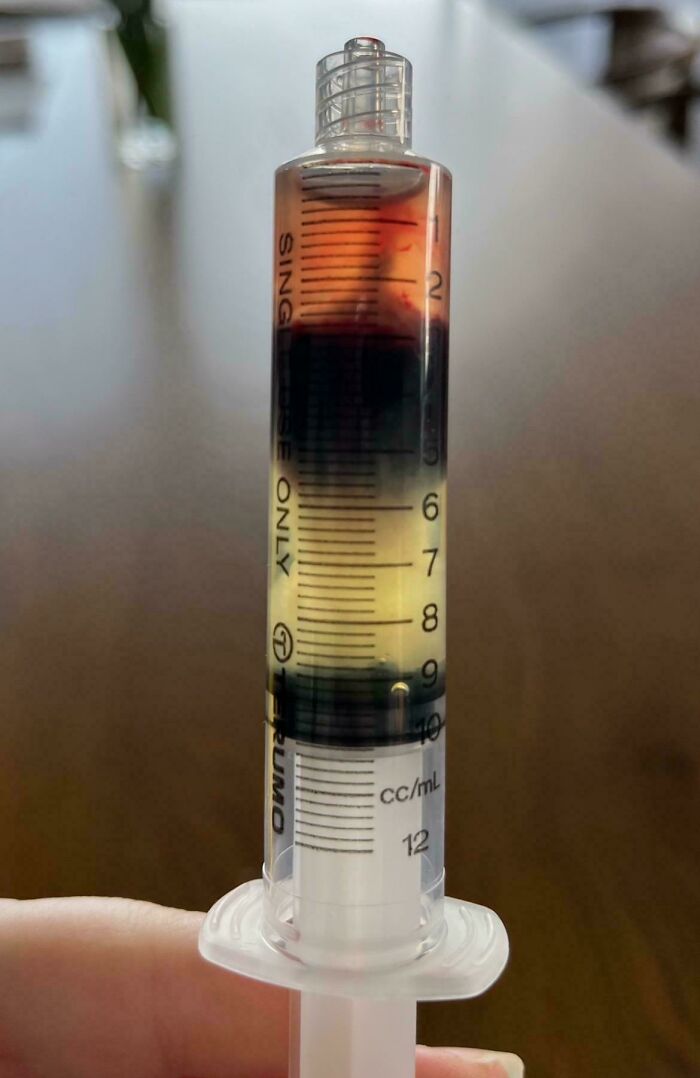

My Blood After Having Separated (Approx 24 Hours Post Collection)

Blood separates into layers because its components—plasma, red blood cells, and white blood cells and platelets—have different densities. When blood is no longer in motion, gravity causes the heavier, denser components, such as red blood cells, to settle to the bottom, while the lighter components, like plasma, remain at the top. This process can also be accelerated by using a centrifuge to spin the blood sample at high speeds, applying centrifugal force to separate the layers based on density.